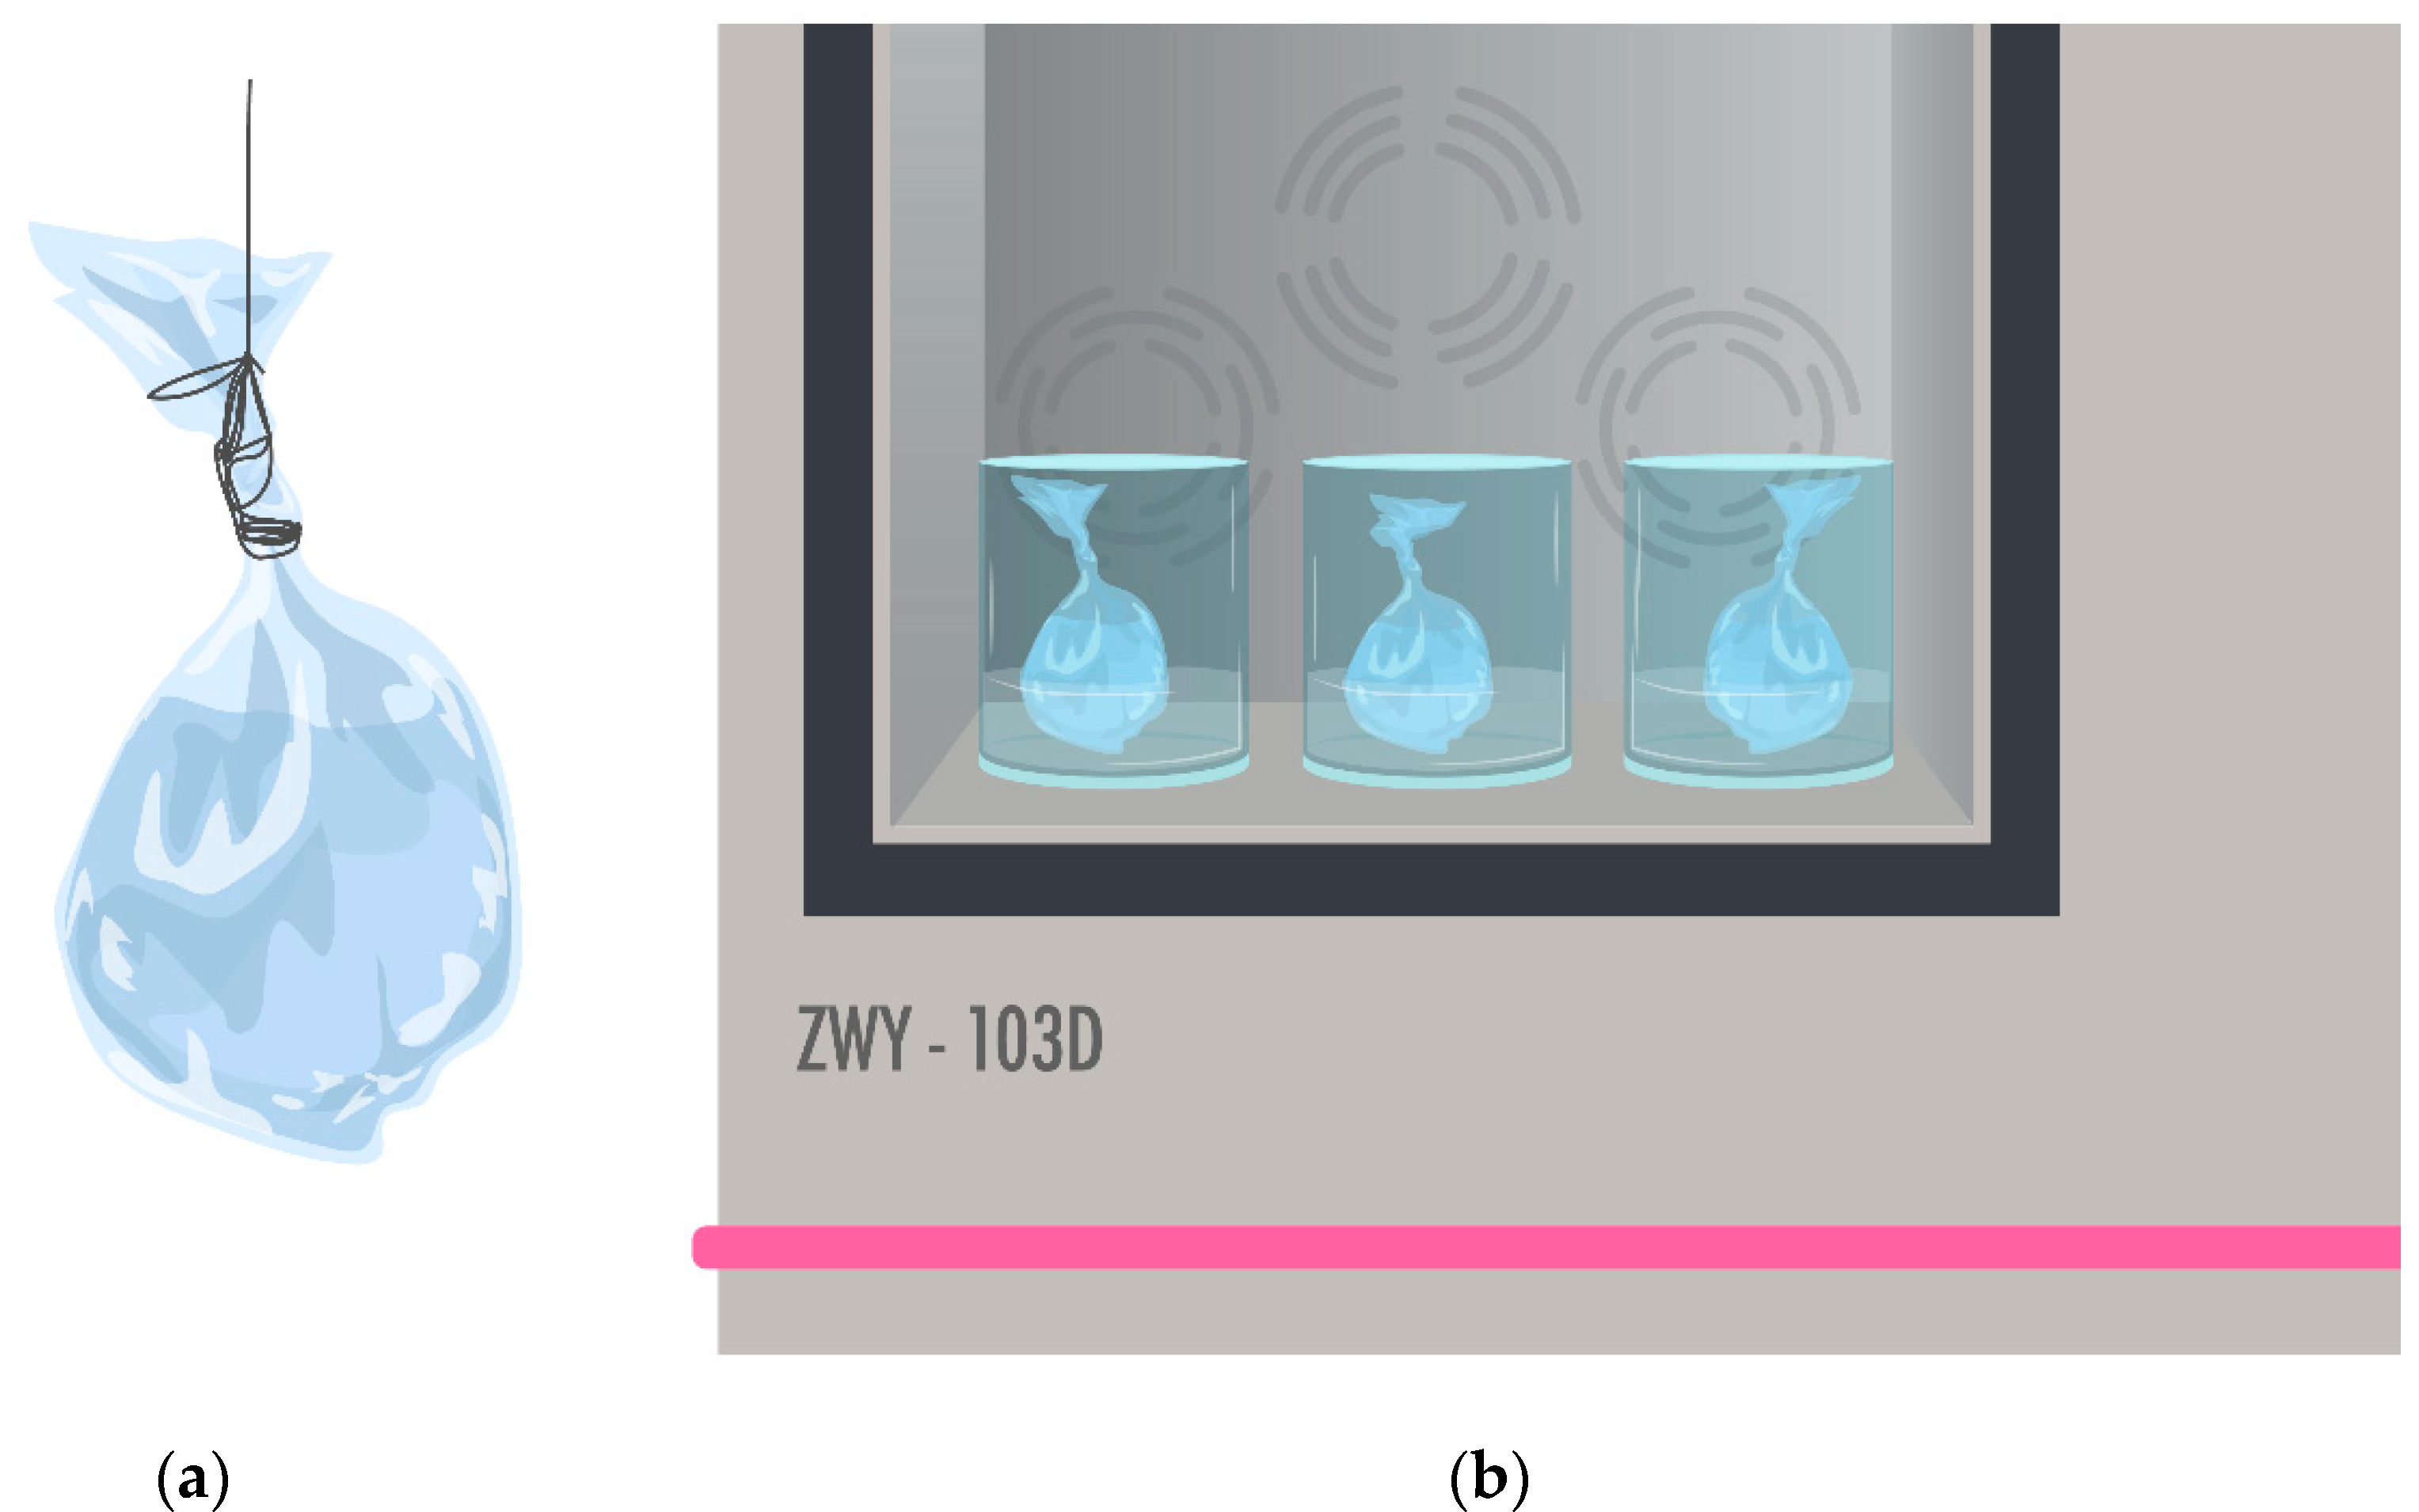

2.6.2. Drug Release Profiles